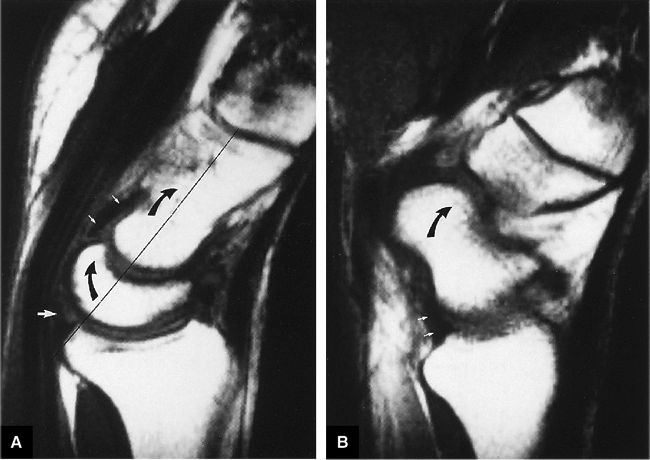

FIGURE 10.85 ● (A) In wrist dorsiflexion, there is colinear alignment (long thin black line) of the dorsiflexed capitate and lunate (curved arrows). The deltoid or arcuate ligament (small white arrows) and the radiolunate (short radiolunate) ligament (large white arrow) are also indicated. Dorsiflexion occurs primarily at the radiocarpal joint. (B) The radioscaphocapitate ligament (small white arrows) also tightens during wrist dorsiflexion, locking any motion between the proximal and distal carpal rows and creating a sling across the waist of the scaphoid. Both the scaphoid (curved arrow) and capitate are thus dorsiflexed.

|